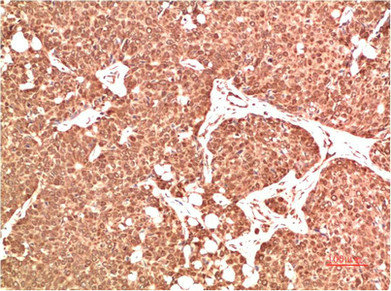

Immunohistochemical analysis of paraffin-embedded Human Breast Carcinoma Tissue using ATM Rabbit pAb diluted at 1:500.